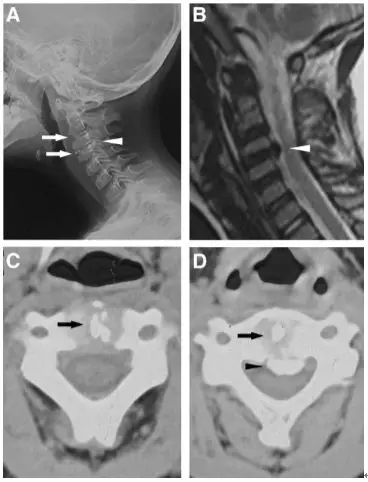

一位88歲女性患者,主訴急性頸痛伴發熱2個月入院。體溫波動在38-39.3℃,無視力模糊,無神經及脊髓壓迫徵象。頸椎CT+矢狀位重建顯示寰椎橫韌帶的曲線狀鈣化(圖A,箭頭所示),線性鈣化(圖B,箭頭所示),以及齒狀突周圍的冠狀鈣沉積(圖C,箭頭所示)。給予短期非甾體抗炎藥和潑尼松龍(15mg/d)後,其上述症狀完全緩解。同時,作者指出這類疾病通常不需要長期用藥。

一位84歲的男性患者,因“急性頸痛、僵硬伴發熱”就診。查體:頸椎向各個方向活動受限,無明顯神經病變體徵。實驗室檢查:血沉及C反應蛋白偏高。頸椎CT平掃提示齒狀突橫韌帶鈣化(箭頭所示),從而診斷為齒狀突加冠綜合徵。給予洛索洛芬治療一週後,上述症狀完全緩解,而且炎性指標恢復正常。

患者女,76歲。無明顯誘因下出現頸部疼痛、僵硬伴發熱 3 d 入院 ,頸部疼痛呈間歇性,頸痛視覺模擬評分(VAS)為7分,體溫37.7~38.8℃,無四肢疼痛麻木,無行走不穩,二便正常。既往無痛風、類風溼關節炎病史。入院體檢:頸椎旋轉明顯受限,頸部肌肉僵硬,未查及明顯神經或脊髓損傷體徵。實驗室檢查:白細胞11.2×109/L,紅細胞沉降率35.4 mm/h,超敏C反應蛋白14.7 mg/L,類風溼因子及降鈣素原正常。頸椎CT平掃示齒狀突後側寰椎橫韌帶弧形鈣化(左圖箭頭)和豎直線樣鈣化(右圖箭頭)。依據患者病史、體徵及輔助檢查,齒狀突加冠綜合徵可基本診斷。入院後給予氯諾昔康 8 mg靜脈滴注每日2次,地塞米松起始量10 mg靜脈滴注每日1次,3日後改為5mg/d。連續治療5 d後,患者入院時症狀明顯緩解,複查白細胞、紅細胞沉降率、超敏C反應蛋白均恢復正常。隨訪半年,未有頸痛伴發熱症狀出現。